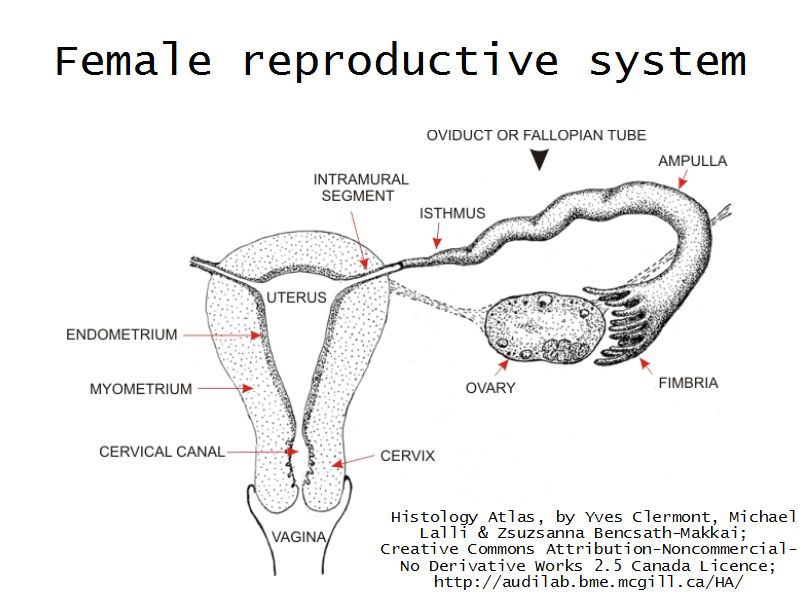

Tuba uterina

Slide 97

Also:

OviductFallopian tube

Uterine tube

Tuba uterina

- Muscular tube

- Most frequent site of fertilization

- Conveys zygote to uterus

- Four regions

- Three layers

Four regions

- Infundibulum

- Ampulla

- Usual site of fertilization

- Isthmus

- Pars interstitialis

- Passes through wall of uterus

Three layers

- Mucosa

- Muscular layer

- Serosa

Mucosa

- Epithelium

- Lamina propria

Epithelium

- Simple columnar

- 2 types of cells

- Peg cells

- Secretory cell

- Ciliated cells

- Beats towards uterus

- Facilitate movement of zygote to uterus

Lamina propria

- Loose connective tissue

- Reticular fibres

- Fibroblasts

- Mast cells

- Lymphoid cells

Muscular layer

- Ill-defined

- Inner circular

- Outer longitudinal

- Play role in moving zygote towards uterus

Serosa

- Simple squamous epithelium

- Contains

- Blood vessels

- Lymphatics

- Nerves

Uterus

Uterus

3 regions3 layers

Three regions

FundusBody

Cervix

Three layers

- Endometrium

- Formation placenta

- Myometrium

- Enlarge during pregnancy

- Expulsion fetus & placenta

- Adventitia

Cervix

- Uterus projecting into vagina

- Dense collagenous CT

- Elastic fibres

- Some smooth muscle fibres

- Simple columnar epithelium

- Transition to stratified squamous

- Cervical glands

Vagina

Vagina

- Fibromuscular tube with 3 layers

- Inner mucosa

- Middle muscle layer

- External adventitia